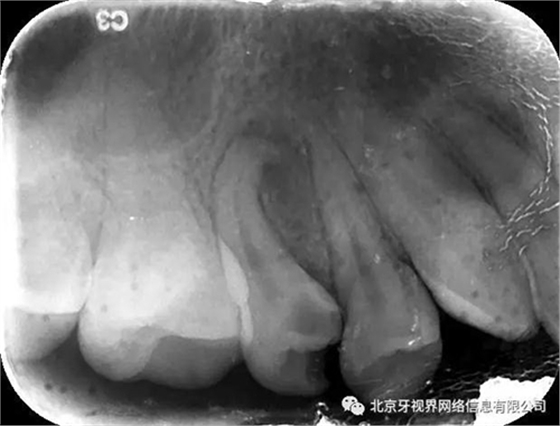

查體:15近中洞,大量腐質(zhì)達髓腔,探痛(—)叩診(+++)冷診無反應,根尖區(qū)牙齦紅腫,無明顯波動感,捫診(+)

輔助檢查:15根尖周低密度影像,根尖1/3向近中彎曲

(1)15根尖周低密度影像結(jié)合查體診斷根尖周炎,根尖中下段明顯彎曲,能否疏通全長,順利抵達根尖區(qū)為術(shù)者首要考慮。